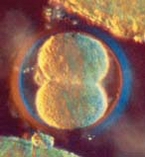

Заченат е нов живот. Яйцеклетката се е срещнала със сперматозоида в маточната тръба. Сляли са се и са образували една обща клетка - зигота. Тя от своя страна е започнала усилено да се дели (от една клетка са се образували две, от 2 - 4, от 4 - 8 и т. н. ). Образувало се е яйце (плодно яйце).

А през това време клетките вътре във вас се делят и размножават, придвижвайки се към матката. Там те ще се прикрепят и ще растат в продължение на следващите 40 седмици."

"Зачатието е вече минало. Новосъздаденият човек започва своя път. В следващите 40 седмици той ще се превърне от микроскопично създание в бебе с тегло от около три килограма и ръст от половин метър. Оплодената клетка се дели и докато се спуска в матката. Тя вече се състои от около трийсетина клетки. Отсега тялото ви знае дали ще имате момче или момиче. Съединявайки се, женската и мъжката яйцеклетка образуват неповторима комбинация от хромозоми. Една двойка от нея отговаря за пола на детето. Ако се е получил чифт XX, то вие ще имате момиче, ако той е XY - момче. В този период вие още не можете да разберете какъв е полът на бебето. Най-рано това може да стане след 6 седмици, когато е възможно да се проведе специално изследване. Чрез ултразвуково изследване полът се установява едва след двадесетата седмица на бремеността. |